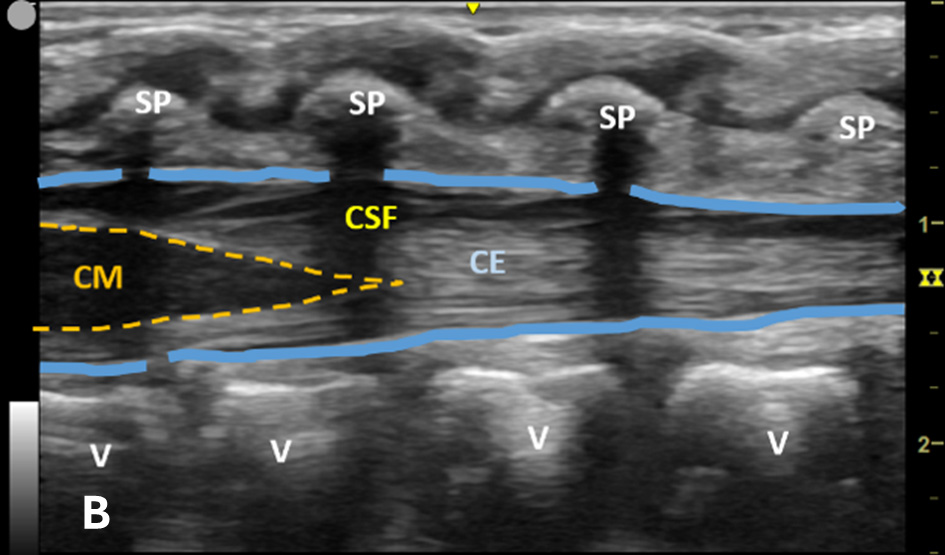

US-assisted LP is performed using the high-frequency linear transducer at the infant’s lower lumbar spine, with the patient either in a lateral recumbent position or an upright sitting position. The standard LP position, in which the neck and hips are flexed, should be used to locate the optimal site for needle insertion. Warm gel should be used during US to provide comfort and reduce the risk of hypothermia in infants. Align the transducer along the spinous process of the lumbar spine above the level of intercristal line to obtain a sagittal view of the spinal canal. The tapered CM is identified, below which any space is safe for needle insertion. The amount of anechoic cerebrospinal fluid (CSF) can be grossly compared in each space to locate the ideal LP site to obtain maximal CSF volume. (Figure 1A-B) The next step is to mark the skin at this optimal intervertebral level using a marking pen. Additionally, we recommend measuring the depth from the skin to the posterior border of the subarachnoid space using calipers, ensuring an angle of entry of 30–45 degrees. (Figure 1C) This allows the proceduralist to more precisely estimate the minimum needle depth needed to reach the subarachnoid space.

Figure 1B - Structures in the target area: SP (spinous process), CSF (cerebrospinal fluid), CM (conus medullaris), and CE (cauda equina).